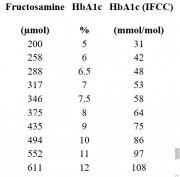

| 15:45, 19 בפברואר 2016 | פרוקטוזאמין4.png (קובץ) |  |

17 קילו־בייטים | Motyk | 1 | |

| 15:34, 19 בפברואר 2016 | פרוקטוזאמין3.png (קובץ) |  |

16 קילו־בייטים | Motyk | 1 | |

| 15:14, 19 בפברואר 2016 | פרוקטוזאמין2.png (קובץ) | 2 קילו־בייטים | Motyk | 1 | ||

| 15:11, 19 בפברואר 2016 | פרוקטוזאמין1.png (קובץ) | 1 קילו־בייטים | Motyk | 1 | ||